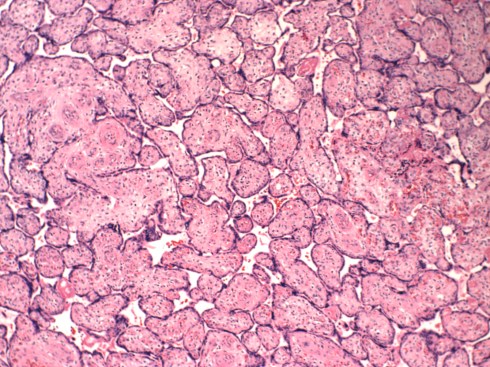

Current terminology emphasizes the endothelial and stromal karyorrhexsis (apoptosis of nuclei). The end result of occlusion of flow to these end villi is the loss of capillary walls, and an increase in collagen throughout the previously loose stroma creating dense pink empty villi under the microscope, designated avascular villi (Fig 18).

Fig 18: The villi in this picture have an eosinophilic (pink) stroma and absent capillaries. The small villi in the center show blue lines (ferrugination) just below the surface that is due to the deposition of iron transported by the syncytiotrophoblast to the stroma in the absence of circulatory transport back to the fetus. (H&E, 20x)